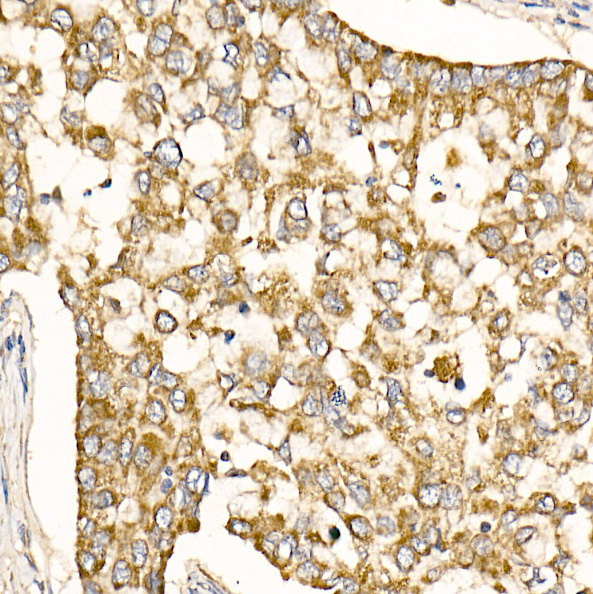

Immunohistochemistry of paraffin-embedded human breast cancer using Prohibitin Rabbit pAb.

Immunohistochemistry of paraffin-embedded human lung cancer using Prohibitin Rabbit pAb.